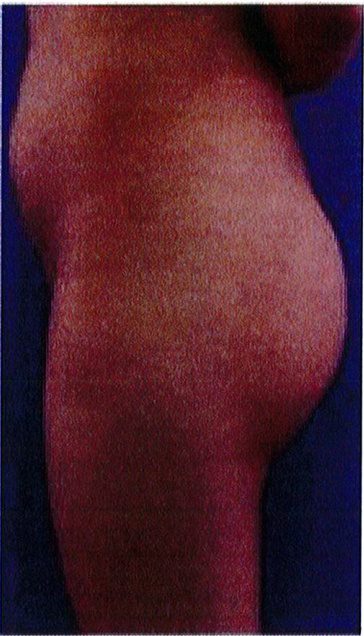

Hình. 20. (A) Hình anh trước và (B) và sau phẫu thuật làm đầy mông của bệnh nhân có vùng mông tương đối đầy đặn. Bệnh nhân được đặt khối implant dưới cân thể tích 330 mL ở hai bên.

THỜI GIAN HỒI PHỤC SAU MỔ

Bệnh nhân 30 tuổi mong muốn cải thiện hình dáng vòng ba, mặc dù vòng mông đã tương đối đây đặn. Bác sĩ sau khi đánh giá đã đưa ra quyết định hút mỡ eo và làm đầy mông bằng implant. Hai khối implant microtextured (vi nhám) thể tích 330 mL được đặt cân đối ở hai bên. Bệnh nhân sau phẫu thuật xuất hiện bục một phần vết mổ (dài khoảng 2cm) ở hai bên nhưng không sâu và đã điều trị kịp thời bằng dung dịch sát khuẩn, kháng sinh tại chỗ và toàn thân. Vết mổ liền lại tốt (Hình 20).